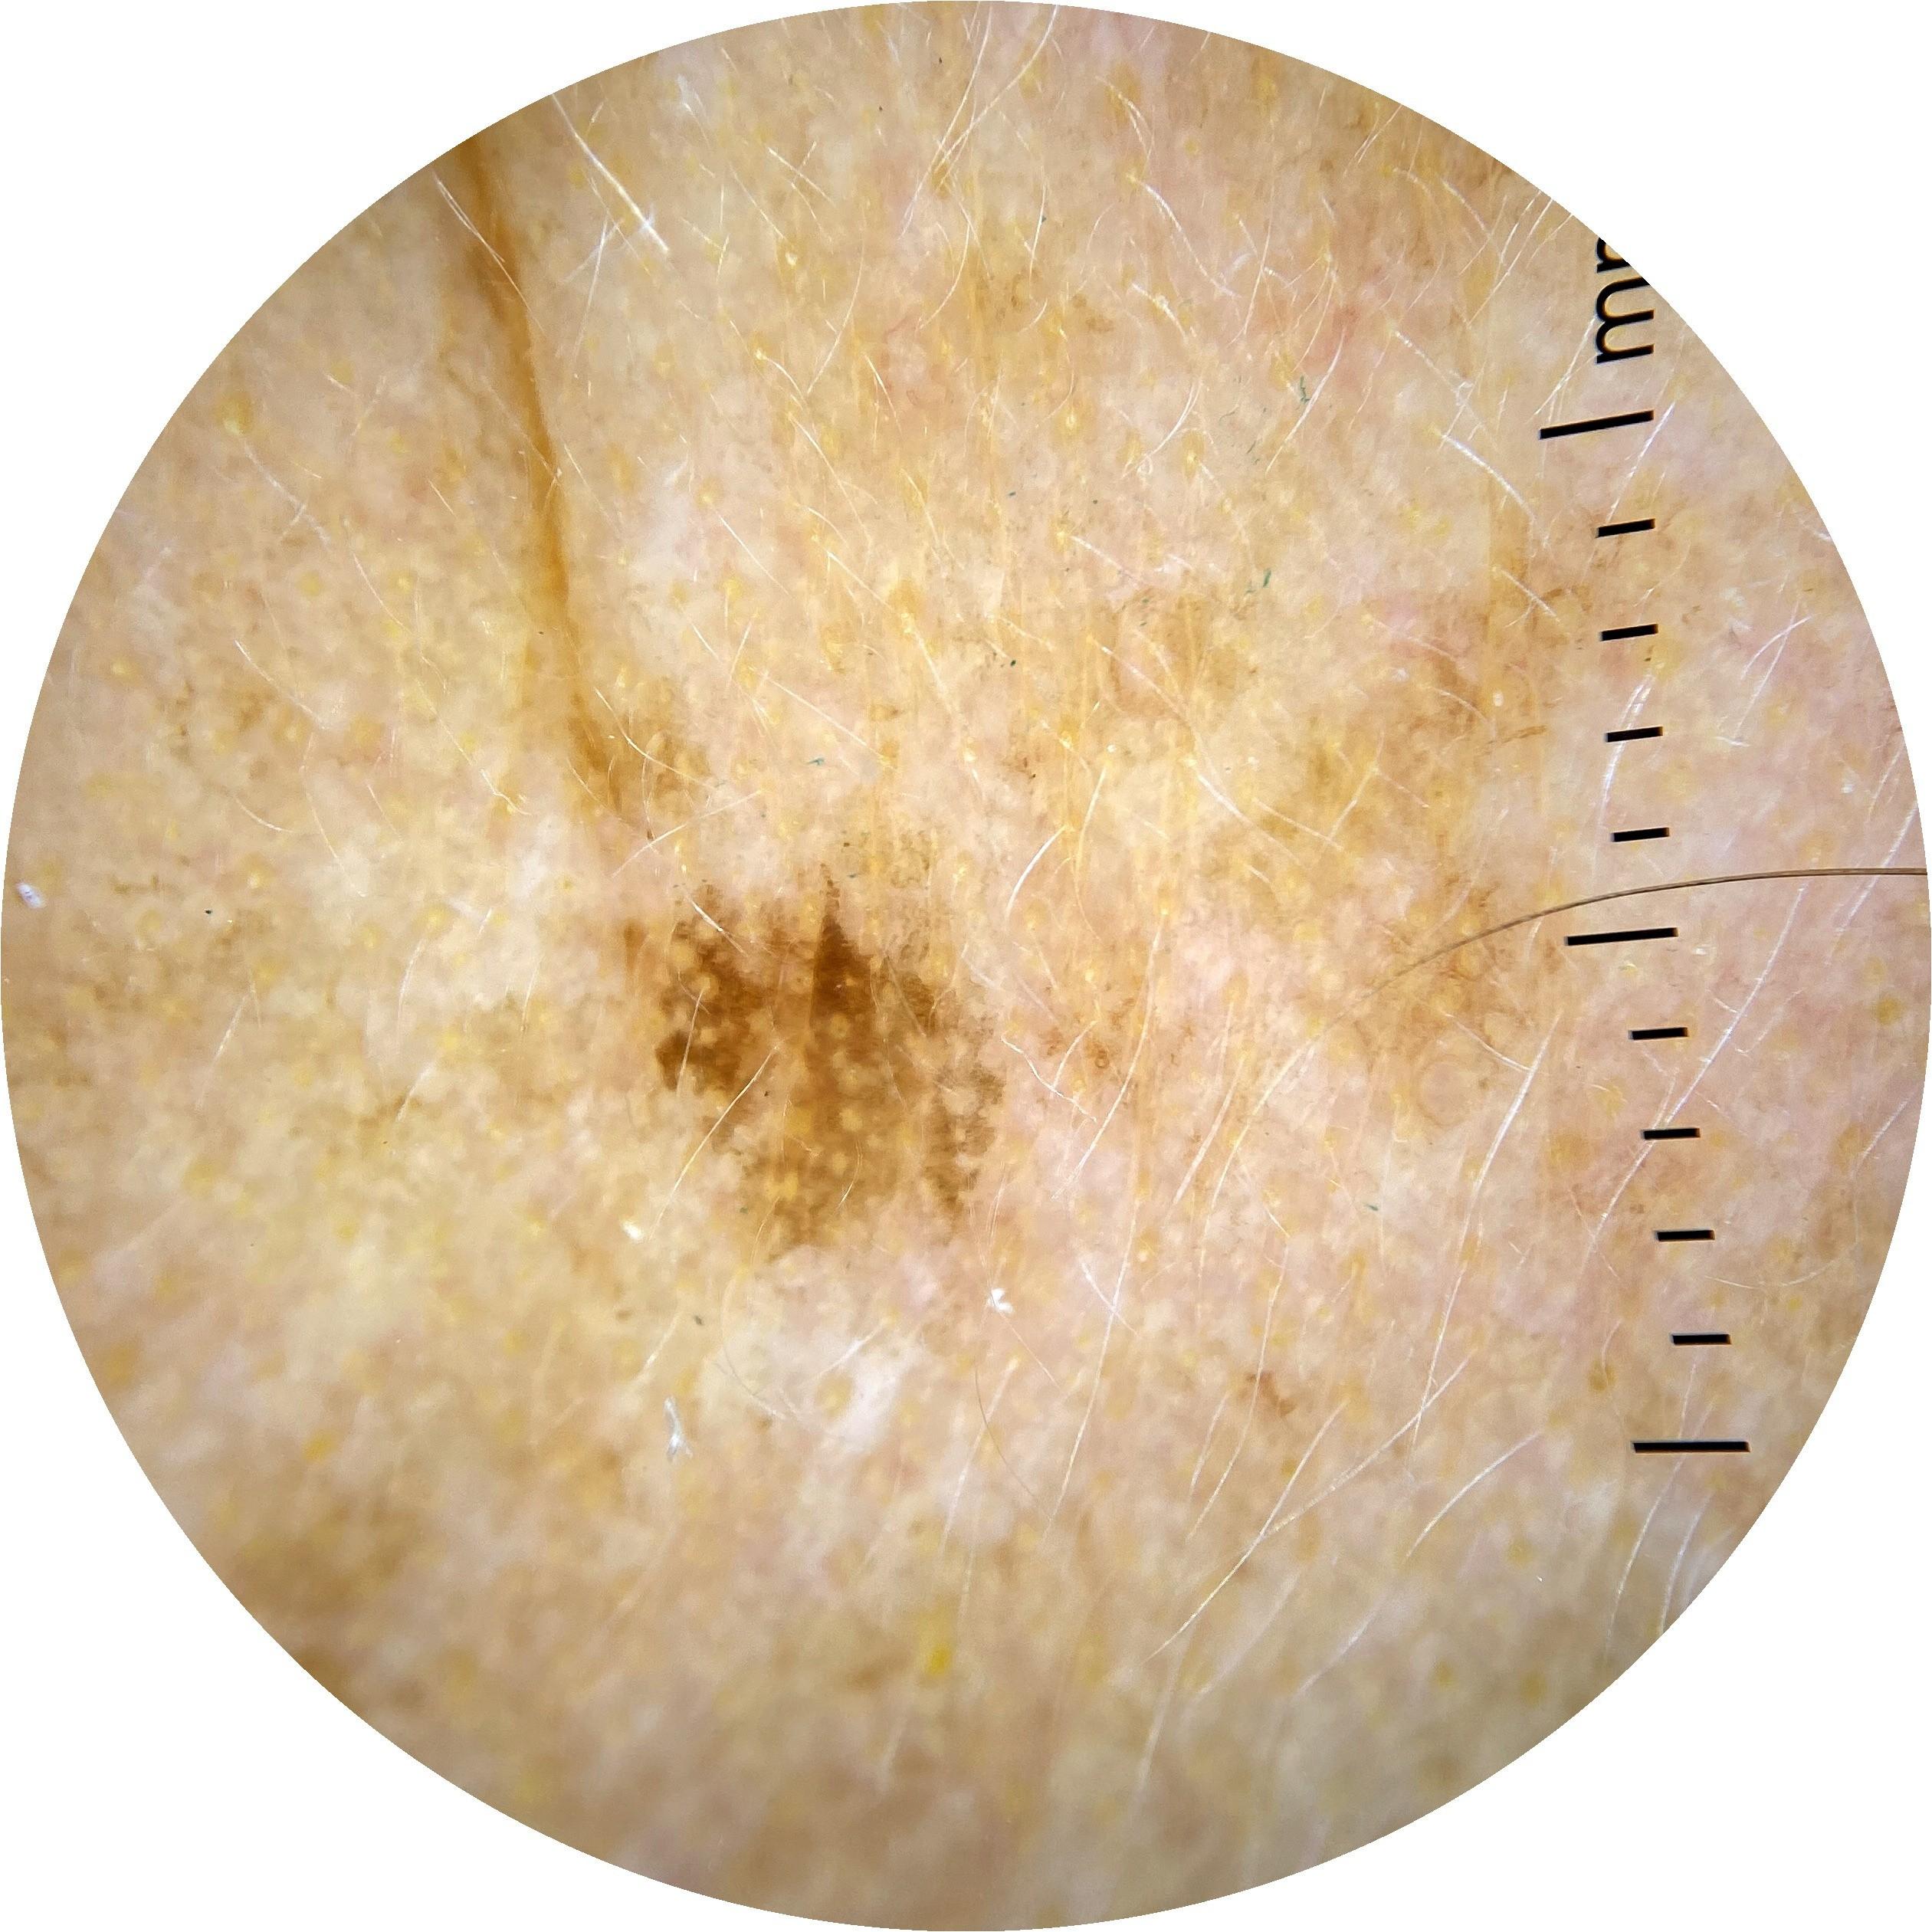

ISIC_7354512

image_type dermoscopic

lesion_id IL_4454105